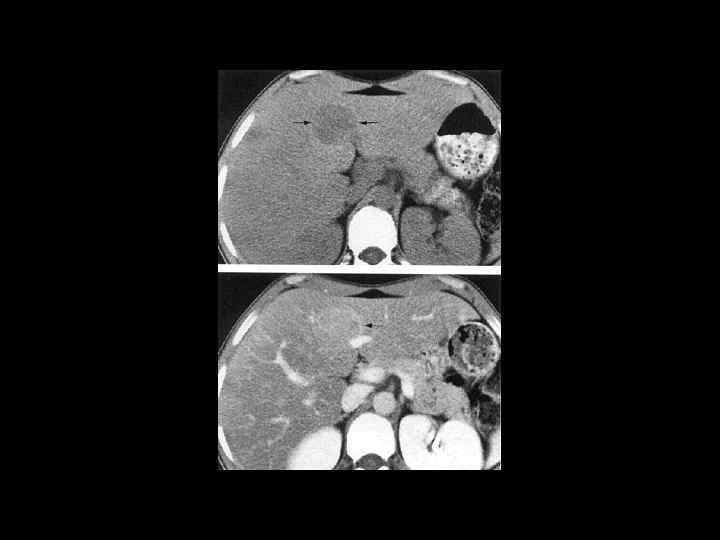

АКТУАЛЬНЫЕ ВОПРОСЫ РЕНТГЕНОЛОГИИ ЛУЧЕВАЯ ДИАГНОСТИКА ОЧАГОВЫХ ПОРАЖЕНИЙ ПЕЧЕНИ АБСЦЕСС ПЕЧЕНИ Компьютерно-томографическая семиотика: - образование низкой плотности (20 -30 ед. Н) - видна капсула с нечетким внутренним контуром - вокруг полости ободок измененной паренхимы - при введении РКВ - усиление изображения стенок

АКТУАЛЬНЫЕ ВОПРОСЫ РЕНТГЕНОЛОГИИ ЛУЧЕВАЯ ДИАГНОСТИКА ОЧАГОВЫХ ПОРАЖЕНИЙ ПЕЧЕНИ АБСЦЕСС ПЕЧЕНИ МР семиотика: - на Т 2 взвешенных изображениях - образования с усиленным сигналом - при контрастном усилении - картина та же, что и при КТ

АКТУАЛЬНЫЕ ВОПРОСЫ РЕНТГЕНОЛОГИИ ЛУЧЕВАЯ ДИАГНОСТИКА ОЧАГОВЫХ ПОРАЖЕНИЙ ПЕЧЕНИ ЗЛОКАЧЕСТВЕННЫЕ ОПУХОЛИ ПЕЧЕНИ Гепатоцеллюлярный рак (гепатома) Компьютерно-томографическая семиотика: - дефект неправильной формы - с неровными, недостаточно четкими контурами - плотность равна или чуть ниже плотности неизмененной паренхимы - после контрастного усиления выраженная неравномерность структуры - часто присутствует инвазия в систему портальной или печеночной вены

АКТУАЛЬНЫЕ ВОПРОСЫ РЕНТГЕНОЛОГИИ ЛУЧЕВАЯ ДИАГНОСТИКА ОЧАГОВЫХ ПОРАЖЕНИЙ ПЕЧЕНИ ЗЛОКАЧЕСТВЕННЫЕ ОПУХОЛИ ПЕЧЕНИ Гепатоцеллюлярный рак (гепатома) МР семиотика: Т 1 взвешенные изображения: - слабо-, изо- или слегка гиперинтенсивный сигнал - повышение сигнала - при богато васкуляризированной опухоли или жировом гепатозе - может визуализироваться ободок капсулы Т 2 взвешенные изображения - повышение интенсивности сигнала и четче видна граница с непораженной тканью После контрастного усиления опухоль видна более отчетливо